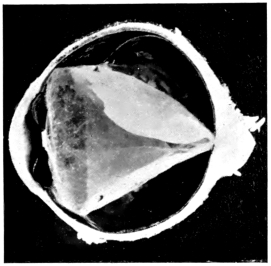

PLATE V.

28.

INJURIES TO UVEAL TRACT

curly bracket span

54

29.

FOREIGN BODY (TIP OF COPPER PROBE) IMBEDDED IN THE EYE

30.

TRAUMATIC DETACHMENT OF RETINA AND CHOROID

31.

WHOLE-SECTION OF FIG. 19

32.

PART OF THE ABOVE MAGNIFIED TO SHOW LENS IMBEDDED IN INFLAMMATORY EXUDATE

33.

PHAGOCYTOSIS